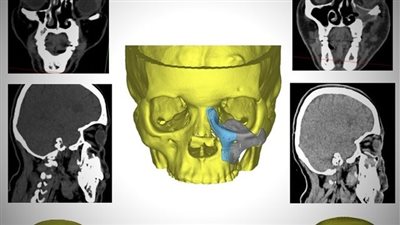

وتُعد زراعة القوقعة عملية جراحية تتضمن زراعة جهاز طبي إلكتروني داخل الأذن الداخلية للأشخاص الذين يعانون فقدانًا شديدًا في السمع نتيجة وجود تلفيات في الأذن الداخلية؛ فيما تساعد عملية زراعة القوقعة على السمع عن طريق تجاوز الأجزاء التالفة من الأذن وتوصيل الإِشارات وتحفيز العصب السمعي للأذن بشكل مباشر.